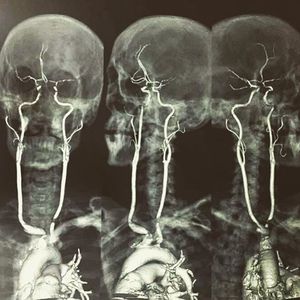

Here is an contrasted MRI showing the origin & length of the carotid arteries. The carotid arteries are major blood vessels in the neck that supply blood to the brain, neck, and face. There are two carotid arteries, one on the right and one on the left. In the neck, each carotid artery branches into two divisions, internal & external carotid arteries. -- Follow us @medshots for more Mention your friends to see this shot!